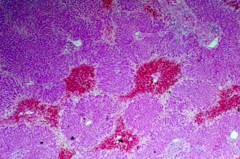

Fat necrosis

Back

-release of pancreatic lipases which cause local destruction of adipocytes -caused by alcoholism, trauma, ischemia, and viral infections -hemorrhagic central areas of liquefaction (firm, gray-white nodules, small chalky white foci with dark hemorrhagic debris -fibrosis-surrounded by fibroblasts -giant cell formation and calcifications -replaced by scar tissue or walled off by fibrous tissue